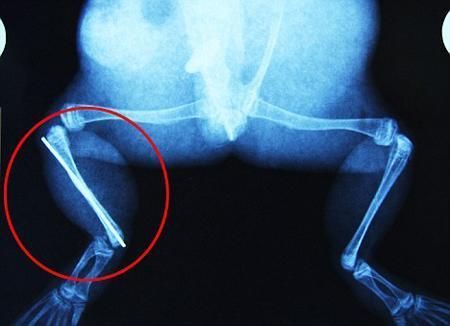

環(huán)球網(wǎng)4月2日報道 據(jù)《每日郵報》報道,上個月,南非大牛蛙布魯萊的右小腿被鄰居家的一只狗咬到,導(dǎo)致粉碎性骨折,現(xiàn)在經(jīng)過2個小時的手術(shù),它的斷腿已經(jīng)被接上,它也因此成為有史以來第一只通過外科手術(shù)用鋼針接上斷腿的青蛙。

布魯萊的主人,居住在南非約翰內(nèi)斯堡附近的62歲的安妮·米恩斯說:“我對這只青蛙如此關(guān)心,人們一定認(rèn)為我瘋了,但是我無法眼睜睜看著它那么痛苦。青蛙因其靈活的腿腳而著稱,一想到布魯萊的腿里要留下一個薄金屬片,我就感到心痛。然而我知道,如果不進(jìn)行手術(shù),布魯萊以后就沒辦法動彈了。因此我匆匆趕到獸醫(yī)那里,央求他給這只可憐的青蛙動手術(shù)。這位獸醫(yī)整天救助小貓小狗,他很難理解為什么我這么擔(dān)心一只青蛙,但是最終他還是答應(yīng)了給布魯萊做手術(shù)。手術(shù)后是幾個小時的焦急等待,我們希望它能快快蘇醒過來。不過現(xiàn)在它的傷口已經(jīng)愈合,又能在花園里跳來跳去了。X光照射顯示,它會恢復(fù)的跟以前一樣。”

野生生物專家安妮經(jīng)常為學(xué)校寫教材,她認(rèn)為這是人類第一次通過手術(shù)給一只青蛙接斷腿。在手術(shù)開始階段,獸醫(yī)把少量給狗用的麻醉藥注入到這只青蛙體內(nèi),讓它失去知覺。然后他在布魯萊的斷腿上切開一個小口,把一根小鋼針植入腿里。最后獸醫(yī)給它縫了9針,把切口縫合在一起。僅僅幾周后,布魯萊就能在安妮家附近活動了。這只青蛙大約已有25歲,主要以嚙齒動物、蛇和其他青蛙為食。布魯萊所屬的牛蛙種群正在不斷減小,目前只能在非洲南部的濕地里才能看到這種青蛙。

安妮有2個孩子,她已經(jīng)從事20多年兩棲動物保護(hù)工作。她認(rèn)為鄰居家的狗狗在把布魯萊從地下刨出來的時候,它正在地下冬眠、她說:“世界上只有這個地區(qū)能看到這種牛蛙,這種青蛙現(xiàn)在變得越來越稀少。因為我從事野生生物保護(hù)工作,因此認(rèn)識很多兩棲動物專家,但是以前他們誰也沒見過這種事情。看到布魯萊越來越健康我非常開心。現(xiàn)在還需要一段時間,它的金屬腿和它的骨骼才能融為一體,那時布魯萊會跟以前一樣健康。我們認(rèn)為這個過程需要幾周時間,但是一旦它完全康復(fù),我希望把它放歸大自然,讓它重新回到它最鐘愛的濕地里。”